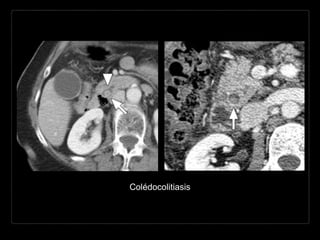

Hallazgos por TC

• densidad del cálculo

aire - < agua - tejidos blandos -

calcio

• mixtas: anillo calcificado y nido central

• ↑ atenuación (75-85%)

• signo “ojo de buey”: anillo de bilis rodeando un cálculo en un

conducto

• colesterol puro = isodensas con la bilis

• terminación abrupta del colédoco

• dilatación de la VBIH y EH

Colédocolitiasis